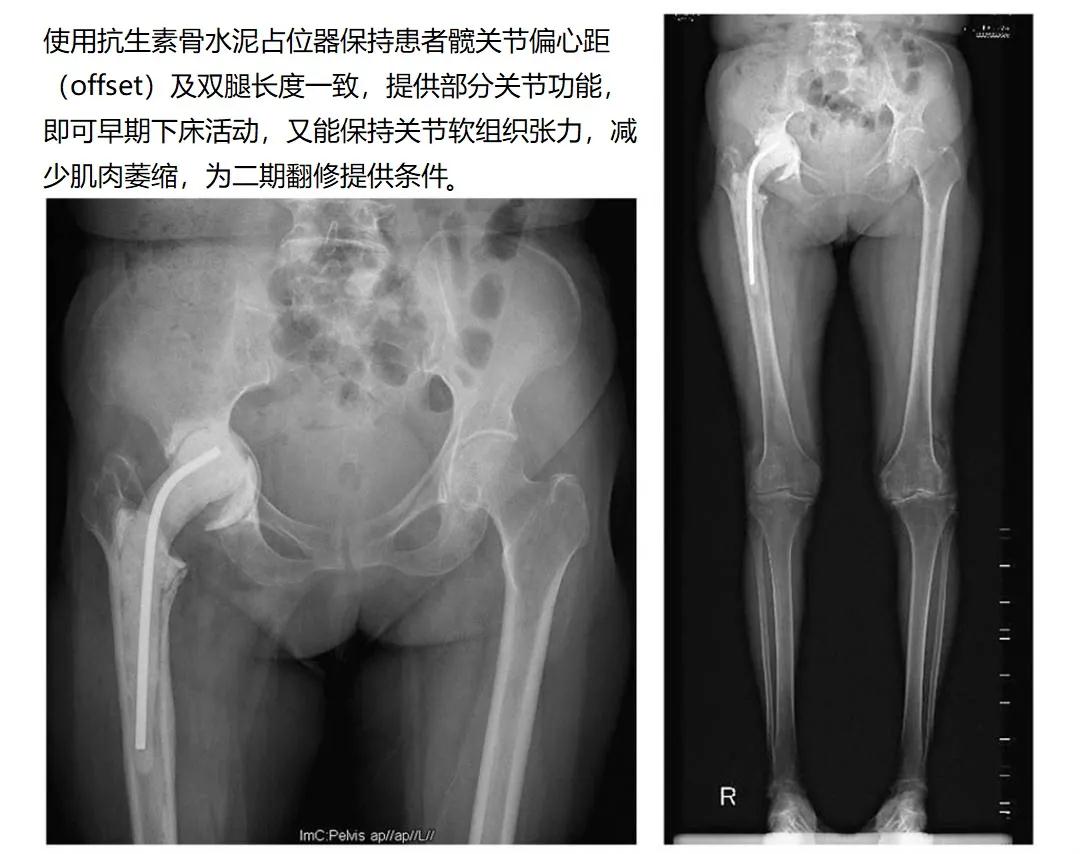

目前,占位器有多种类型,既可直接使用商品化成品,也可术中用骨水泥(含抗生素)定制。骨水泥占位器可以加入敏感抗生素,使关节周围维持较高的局部药物浓度,可以更好地控制感染,而且具有成本低、可塑性好等优势。

骨水泥占位器分为关节型(活动型)和非关节型(固定型)。

关节型:优势为旷置期间可以进行关节活动,减轻瘢痕粘连,术后患者活动范围更好,感染复发率更低,骨丢失更少,为二次手术创造条件。

非关节型:主要起临时固定的作用,可维持关节稳定,保持软组织张力,但长时间关节制动容易导致肌肉萎缩、骨质疏松及瘢痕形成,影响二次手术的效果。适用于更加严重的骨缺损,以及软组织、韧带缺损的患者。

对于上述两种不同类型的骨水泥占位器,多数医师倾向于选择关节型占位器,因其更好地改善关节功能。